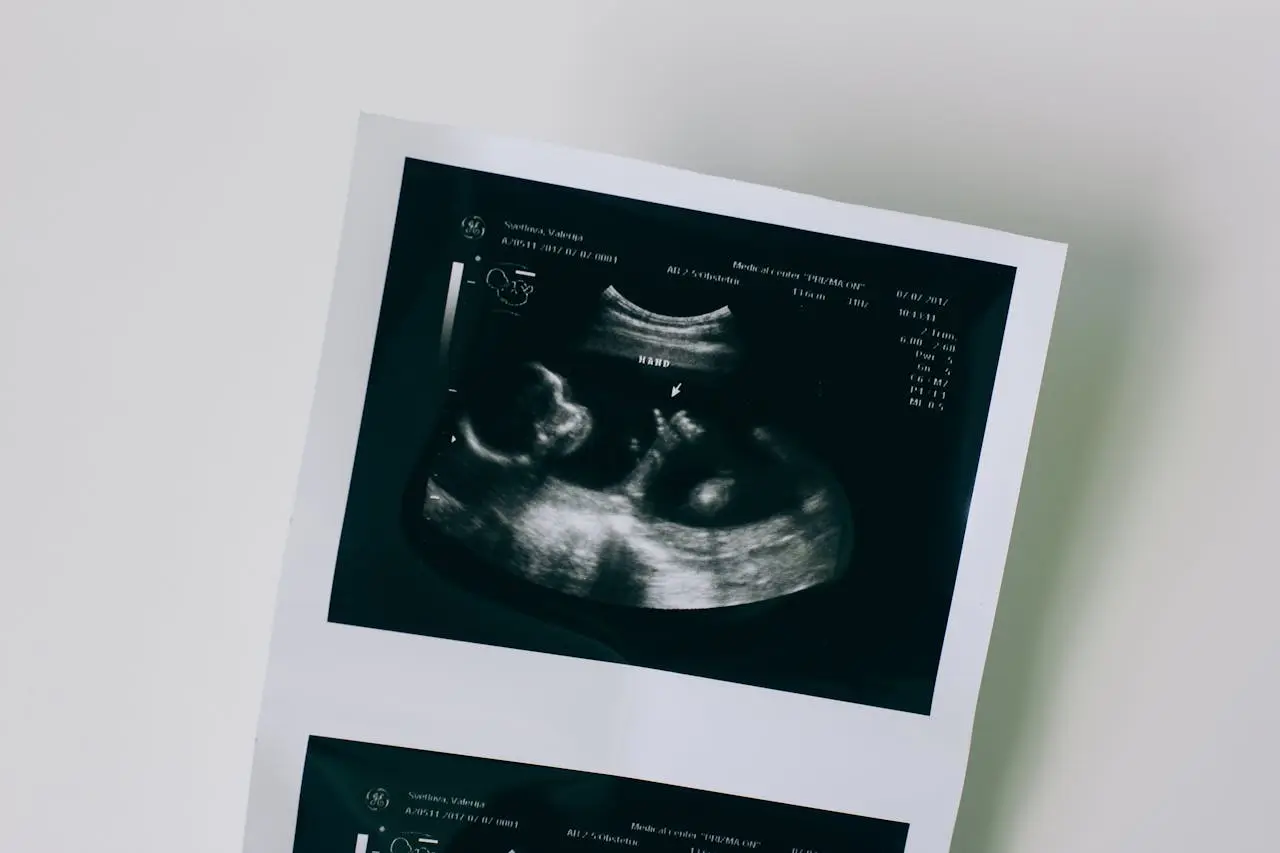

Cancún, MexicoSamsung Medison is capturing global attention with its advanced ultrasound diagnostic solutions tailored to women’s health — spanning every stage of life, from fetal development to menopause.

A major highlight at ISUOG 2025 is the unveiling of the upgraded HERA Z20, a powerful diagnostic system designed to support comprehensive women’s healthcare throughout all life stages — from adolescent gynecological conditions and fertility, to pregnancy, childbirth, and aging.

- Live ViewAssist™: Automatically extracts up to 39 key cross-sectional images, complete with annotations and measurements, across different stages of pregnancy — significantly reducing diagnostic time.

- QualityCheck: Evaluates image quality in real time during fetal exams to ensure consistent diagnostic accuracy and reduce the need for repeat scans.